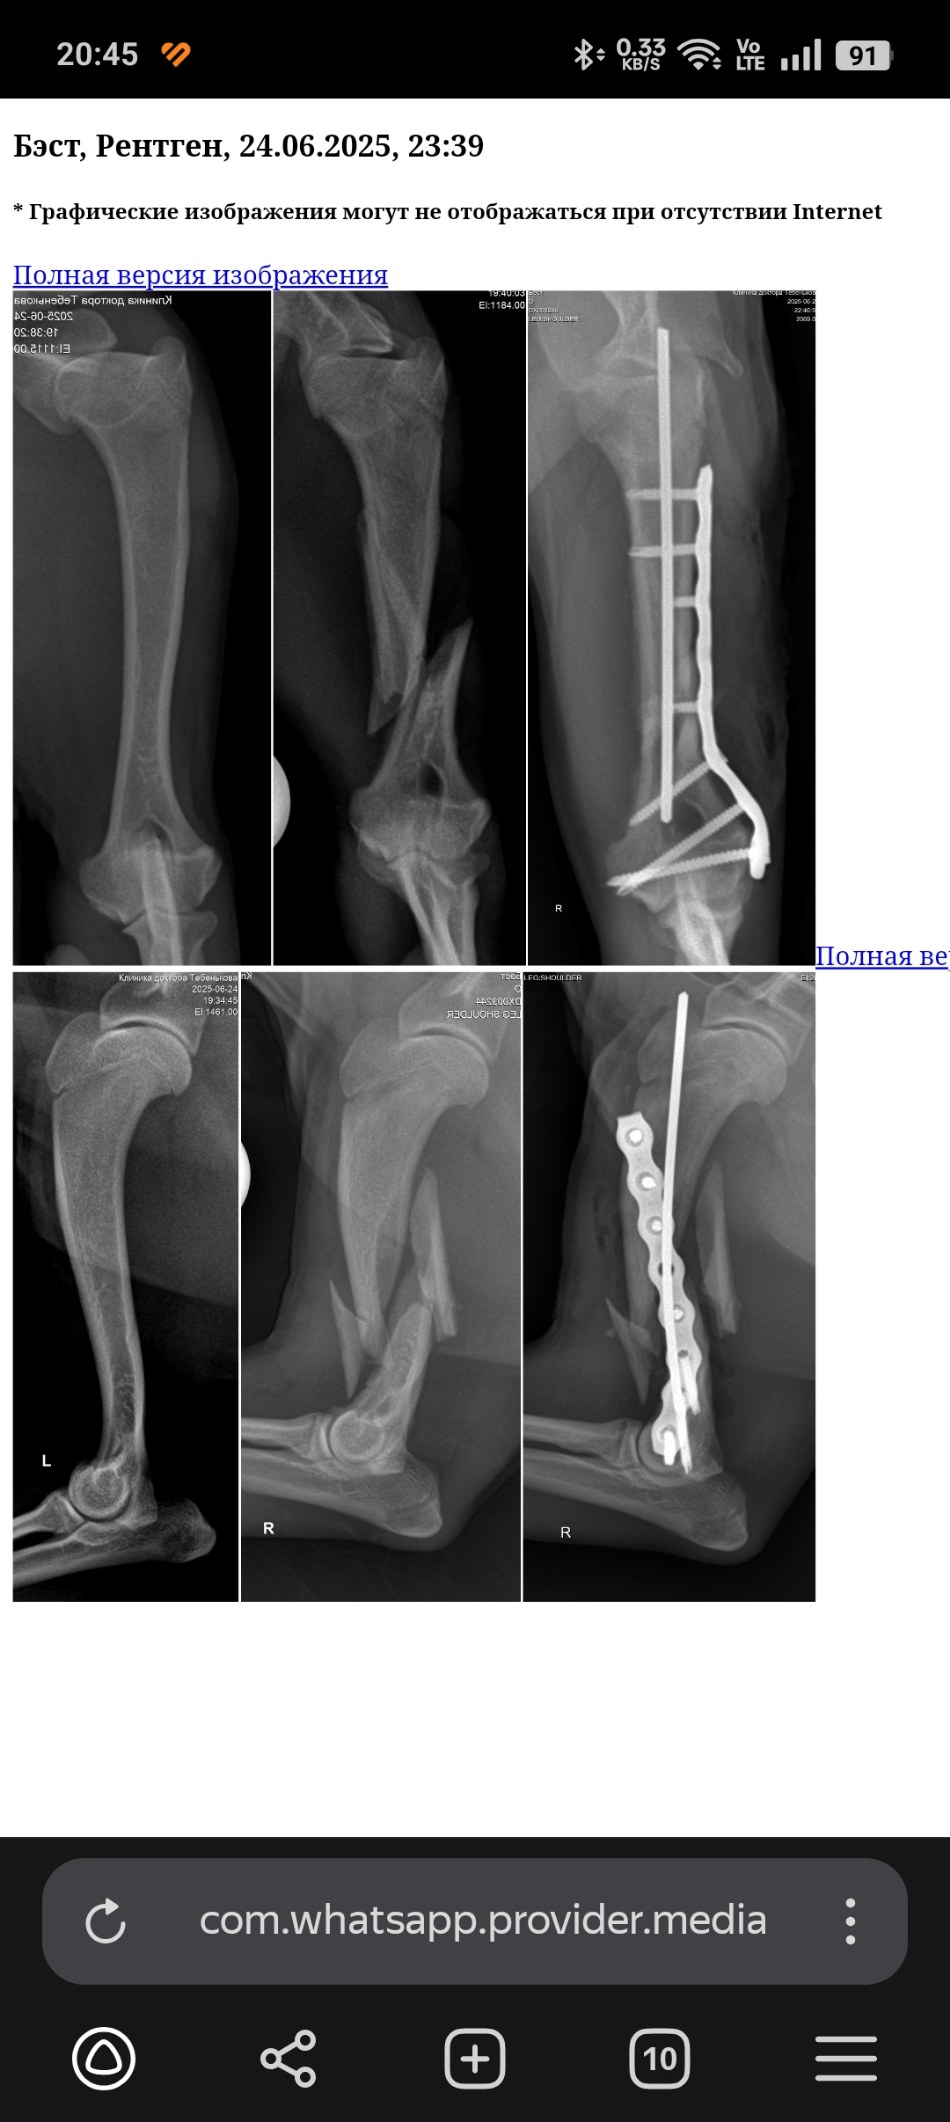

Рентген до и после

Screenshot_2025-06-25-20-45-40-45_21da60175e70af211acc4f26191b7a77.jpg

Найден с переломом плеча.